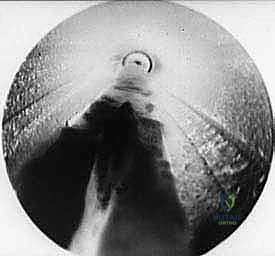

TECH FIG 6 • A. Endoscopic view of transverse intermetatarsal ligament.

TECH FIG 6 • B. Endoscopic view of knife blade transecting the transverse intermetatarsal ligament.